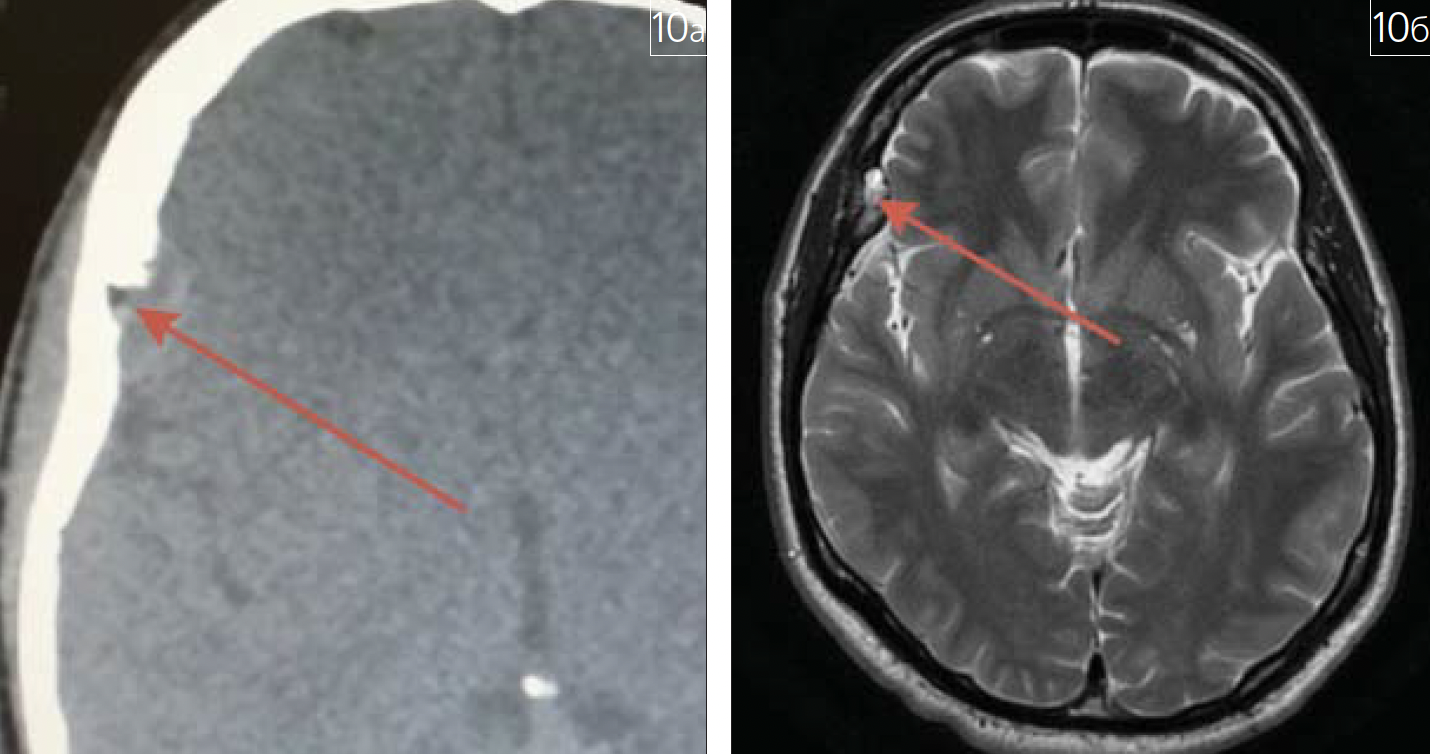

В практике врача-рентгенолога регулярно встречается такое поражение костной ткани, как эозинофильная гранулёма (болезнь Таратынова). Её рентгенологическими признаками являются участки разрежения костной ткани с нечеткими "фестончатыми" контурами без каймы склероза, с возможным разрушением наружной и внутренней замыкательных пластинок костной ткани и инвазией в мягкие ткани, с формированием секвестров (симптом "пуговицы" на рентгенограмме, рис. 10).

Рис. 10. Эозинофильная гранулема на МСКТ и МРТ (зона патологических изменений отмеченана рисунках красной стрелкой): а – МСКТ, аксиальная плоскость; б – МРТ, Т2 ВИ, аксиальная плоскость

Хочется отметить, что данные изменения возможно выявить на рентгеновских снимках, применяемых для рентгеноцефалометрического анализа в практике врача-стоматолога-ортодонта и челюстно-лицевого хирурга. Речь идет о телерентгенограммах (ТРГ) черепа в прямой и боковой проекциях и 3D-цефалометрии.